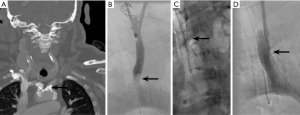

A 75-year-old male with a prior history of symptomatic right ICA and right subclavian stenosis, status post aorto-to-right carotid and right subclavian bypass, presented with left ocular ischemic syndrome from near occlusion of the left ICA, confirmed by CTA (Figure 2A). He also had a concomitant calcific, coral reef plaque causing severe stenosis at the left CCA origin. Cardiovascular risk factors included CHF (EF 63%), hypertension, diabetes mellitus type 2 with diabetic kidney disease stage 4, prior smoking, obesity, and hyperlipidemia. The decision was made to perform a left CEA with retrograde shock wave angioplasty and stenting of the origin of the CCA under EEG monitoring. Through a 7 cm cervical incision on the anterior border of the sternocleidomastoid muscle, the common carotid and its bifurcation were dissected free and controlled with vessel loops. Retrograde access was obtained in the left CCA. Intraoperative angiogram showed a cauliflower-like calcific lesion causing severe stenosis of the origin of the left CCA (Figure 2B). The lesion was crossed intraluminally and angioplastied with 8 cycles of 9 mm shockwave balloon (Figure 2C), followed by stenting with VBX 9 mm × 29 mm stent (Gore & Associates, Inc). The sheaths and wires were removed, and conventional CEA and patch angioplasty were performed. Completion angiogram showed complete expansion of the stent with no residual stenosis, dissection, or contrast extravasation (Figure 2D). At 7-month follow-up, the patient remained neurologically intact, and the stent was patent based on magnetic resonance angiography (MRA).